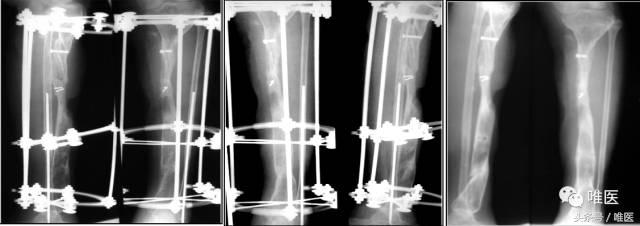

7. 术后随访

二期术后12月:骨缺损完全修复,外架拆除后。

二期术后12月:功能恢复良好